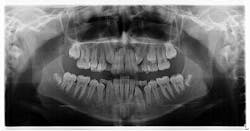

Diagnosis: Mesiodens tooth

For a recap on mesiodens teeth, diagnosis, and treatment, please refer to another case report I wrote that you might find of interest. Here is a quick- The lesions may occur “as single, multiple, unilateral, or bilateral (lesions); the presence of multiple supernumerary teeth is called ‘mesiodentes.’”1

- By way of appearance, they typically manifest in a conical- or peg-shaped form.2

- In general, supernumerary teeth—also referred to as hyperdontia or extra teeth—can occur in any location, but they are more prevalent in the maxilla (90%) as opposed to the mandible (10%).2

- The most common type of supernumerary teeth are mesiodentes.1 Their etiology remains unclear, although it is theorized that they are either an isolated finding or part of a “syndrome, specifically cleft lip and palate, cleidocranial dysostosis, and Gardner’s syndrome.”1

- Diagnosis is primarily via radiograph and can be confirmed by taking multiple angles using intraoral and extraoral radiographs (i.e., panoramic, periapicals, etc.). Furthermore, three-dimensional CBCT scans allow dialing in on the palatal location of the mesiodentes and their relationship to adjacent teeth. Delayed or altered eruptions of adult dentition also give rise to the suspicion of mesiodentes. Other common signs include cyst formation and crowding.

- Treatment of mesiodens varies. Although typically asymptomatic, they are “often extracted for aesthetic reasons, to allow the eruption of other teeth, orthodontic reasons, and/or suspected pathology.”3